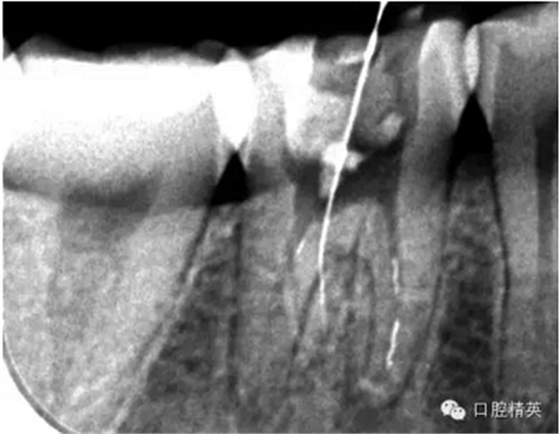

這個也是我目前接到最有難度的器械分離病例,從片子上看近中器械分離兩節(jié),曾在外院做過干尸,有七年。當看到這個病例時我沒有多大的把握,因為我是身處基層,無顯微,無放大。我只有抱著試一試的態(tài)度,但是她是我們院內(nèi)員工,壓力很大。

現(xiàn)在開始看第二張片子我疏通的遠舌根,有點問題哦!~

根尖孔偏移,或者是片子角度問題,導致我們很難判斷,感覺像是測穿。但是我們有根測儀(前提它是好的),因為根測儀是我們目前對根管測量最具有說服力,也是最為客觀事實的。根測儀沒有顯示一探入根尖下三分之一顯示“over”的情況(我用的是登士博根測儀)根管內(nèi)無滲出,可以測出根管的長度。那就證明工作長度的存在,和可信。在看看正題的近中根的器械,我想問問大家覺得是什么器械??

近中舌根疏通,兩根分離的器械都在近中舌根。花費2個多小時。將它疏通下去還是離不開較長的時間,也就是耐心,它真的很重要哦!~第二個我覺得器械分離的疏通,就是在于能否建立旁路,那么怎么去建立這條路。我個人覺得首先挫的選擇,是k挫,是c+,還是別的什么。我的首選是8號c+,因為它夠硬,8號的k挫太軟,沒有辦法擴下去,很容易碰到根內(nèi)部器械導致器械報廢,尖端變光亮。但是c+挫也不是那么完美,我擴的時候用了4根8號新的c+挫,全部報廢。尖端彎曲90度的,有變成麻花的。這些都在提醒我可能用力過大,或者根管內(nèi)部太過于復雜。疏通時只有慢慢來,一點點的下千萬不要妄想一步到位。手法還是要輕柔否則你的器械一樣也會分離進去。疏通到挎自己的器械的時候也是碰到分離的器械時,這個時候最好是上下提拉,切勿旋轉(zhuǎn)向下,你只有盡量將該部位擴開,為下一步往下疏通留有足夠的空間就好。而不是繼續(xù)向下旋轉(zhuǎn),這樣會導致器械的分離,加大你疏通的難度。